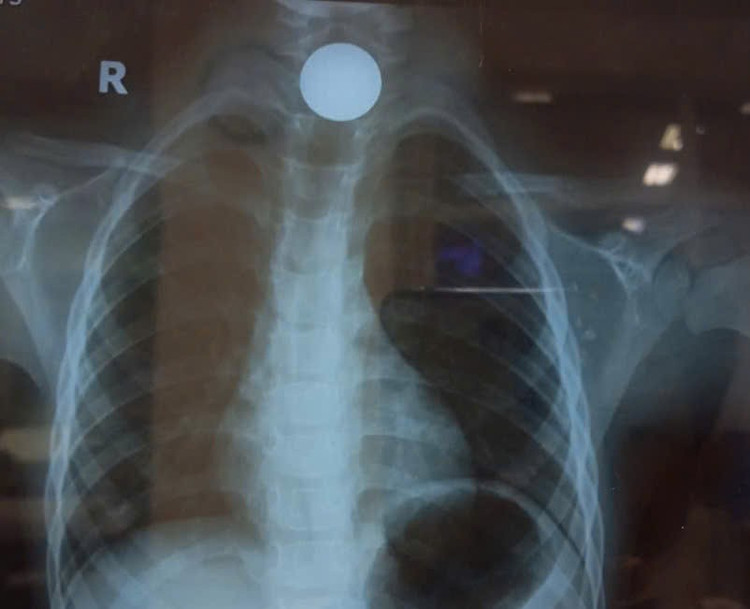

Tại đây, các bác sĩ nhanh chóng thăm khám và chỉ định chụp X-quang. Hình ảnh cho thấy tại vị trí miệng thực quản có một dị vật hình tròn, dẹp – đúng như lời kể của gia đình, đó chính là chiếc đồng xu mà bé đã nuốt phải.

dong-xu.jpg

Đồng xu được lấy ra - Ảnh BVCC